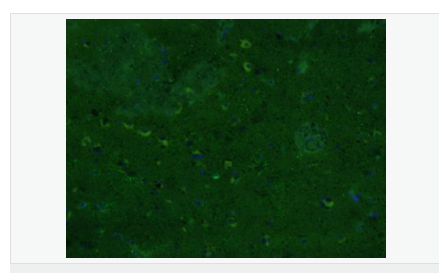

| 产品应用 | WB=1:500-2000 ELISA=1:5000-10000 IHC-P=1:200-1000 IHC-F=1:200-1000 Flow-Cyt=1μg/Test ICC=1:100 IF=1:200-800 (石蜡切片需做抗原修复) not yet tested in other applications. optimal dilutions/concentrations should be determined by the end user. |

| 产品介绍 | This gene encodes one of the major intermediate filament proteins of mature astrocytes. It is used as a marker to distinguish astrocytes from other glial cells during development. Mutations in this gene cause Alexander disease, a rare disorder of astrocytes in the central nervous system. Alternative splicing results in multiple transcript variants encoding distinct isoforms. [provided by RefSeq, Oct 2008] Function: GFAP, a class-III intermediate filament, is a cell-specific marker that, during the development of the central nervous system, distinguishes astrocytes from other glial cells. Subunit: Interacts with SYNM. Isoform 3 interacts with PSEN1 (via N-terminus). Subcellular Location: Cytoplasm. Note=Associated with intermediate filaments. Tissue Specificity: Expressed in cells lacking fibronectin. Post-translational modifications: Phosphorylated by PKN1. DISEASE: Defects in GFAP are a cause of Alexander disease (ALEXD) [MIM:203450]. Alexander disease is a rare disorder of the central nervous system. It is a progressive leukoencephalopathy whose hallmark is the widespread accumulation of Rosenthal fibers which are cytoplasmic inclusions in astrocytes. The most common form affects infants and young children, and is characterized by progressive failure of central myelination, usually leading to death usually within the first decade. Infants with Alexander disease develop a leukoencephalopathy with macrocephaly, seizures, and psychomotor retardation. Patients with juvenile or adult forms typically experience ataxia, bulbar signs and spasticity, and a more slowly progressive course. Similarity: Belongs to the intermediate filament family. SWISS: P14136 Gene ID: 2670 Database links: Entrez Gene: 2670 Human Entrez Gene: 14580 Mouse Omim: 137780 Human SwissProt: P14136 Human SwissProt: P03995 Mouse Important Note: This product as supplied is intended for research use only, not for use in human, therapeutic or diagnostic applications. 星形胶质细胞标志物 (Astrocyte Marker) GFAP是一个56kDa的中间丝蛋白(intermediate filament,IF),在中枢神经系统发育期是一个特异性的标志物,以区别星形细胞和其它胶质细胞。GFAP表达在皮层和海马,急、慢性皮质酮治疗时表达减少。 GFAP可以和人、大鼠、小鼠的GFAP反应,在正常和肿瘤性的星形胶质细胞阳性表达,而神经节细胞、神经元、成纤维细胞、少突胶质细胞和这些细胞来源的肿瘤细胞阴性表达,主要用于星形胶质瘤等中枢神经系统肿瘤的诊断和鉴别诊断,GFAP的缺乏可导致AD病。 |